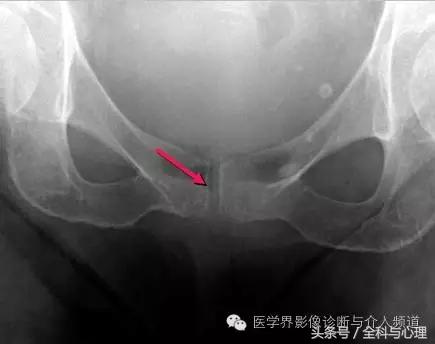

耻骨联合软骨钙化